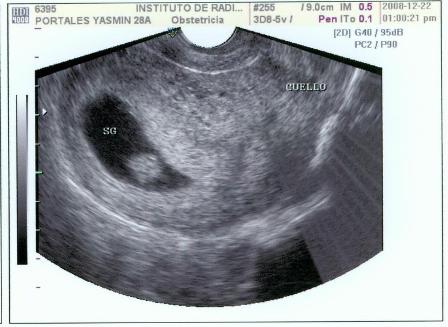

Fotos del 22 Dc 2008:

Informe:

Embrión correspondiente a 9 s cumplidas de embarazo y con FC (frecuencia cardiaca, supongo) de 162 LPM.

Saco gestacional bien conformado y localizado en fondo uterino.

Estructura uniforme de útero con cuello cerrado, ausencia de signos de sangrado gestacional.